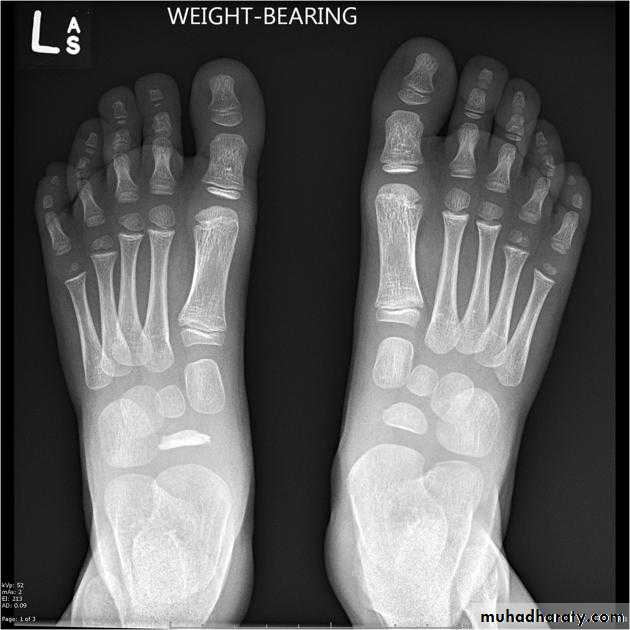

GOUT

• Heterogeneous group of entities characterized by recurrent attacks of arthritis secondary to deposition of sodium urate crystals in and around joints.• *90% of patients are male

• *Causes due to either Uric acid overproduction, 10% or underexcretion, 90%.

• Radiographic features

• *Lower extremity > upper extremity; small joints > large joints

• * First MTP is most common site

• * Marginal, peri articular erosions: overhanging edge

• * Erosions may have sclerotic borders

• * Joint space is preserved

• * Soft tissue and bursa deposition

• Tophi: juxtaarticular, helix of ear

• Bursitis: olecranon, prepatellar

• * Erosions and tophi only seen in longstanding disease

• * Tophi calcification, 50%

• *Chondrocalcinosis